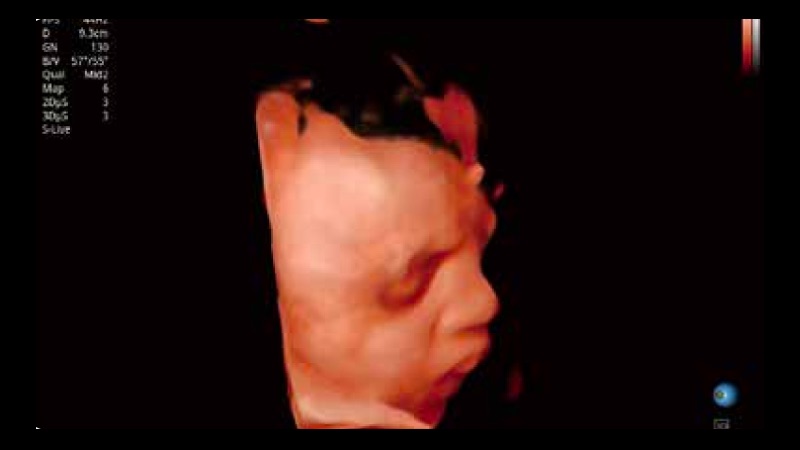

S-Live 高分辨率容积成像

通过仿真成像技术对3D/4D立体数据进行渲染,多种初始光源位置可选,并支持轨迹球360°光源位置自由调节,清晰显示不同方位容积图像细节。